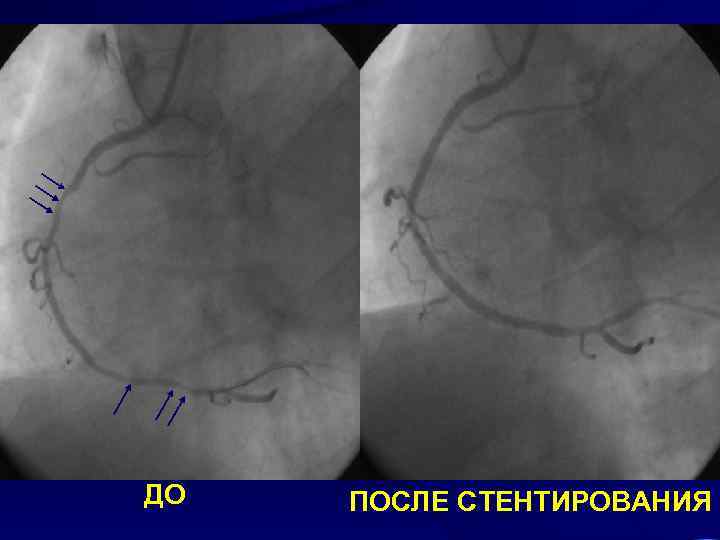

ДО ПОСЛЕ СТЕНТИРОВАНИЯ

Больной Н. 52 лет Диагноз: ИБС: безболевая ишемия миокарда, атипичная стенокардия II ФК. ПНА: стеноз в среднем сегменте до 90%